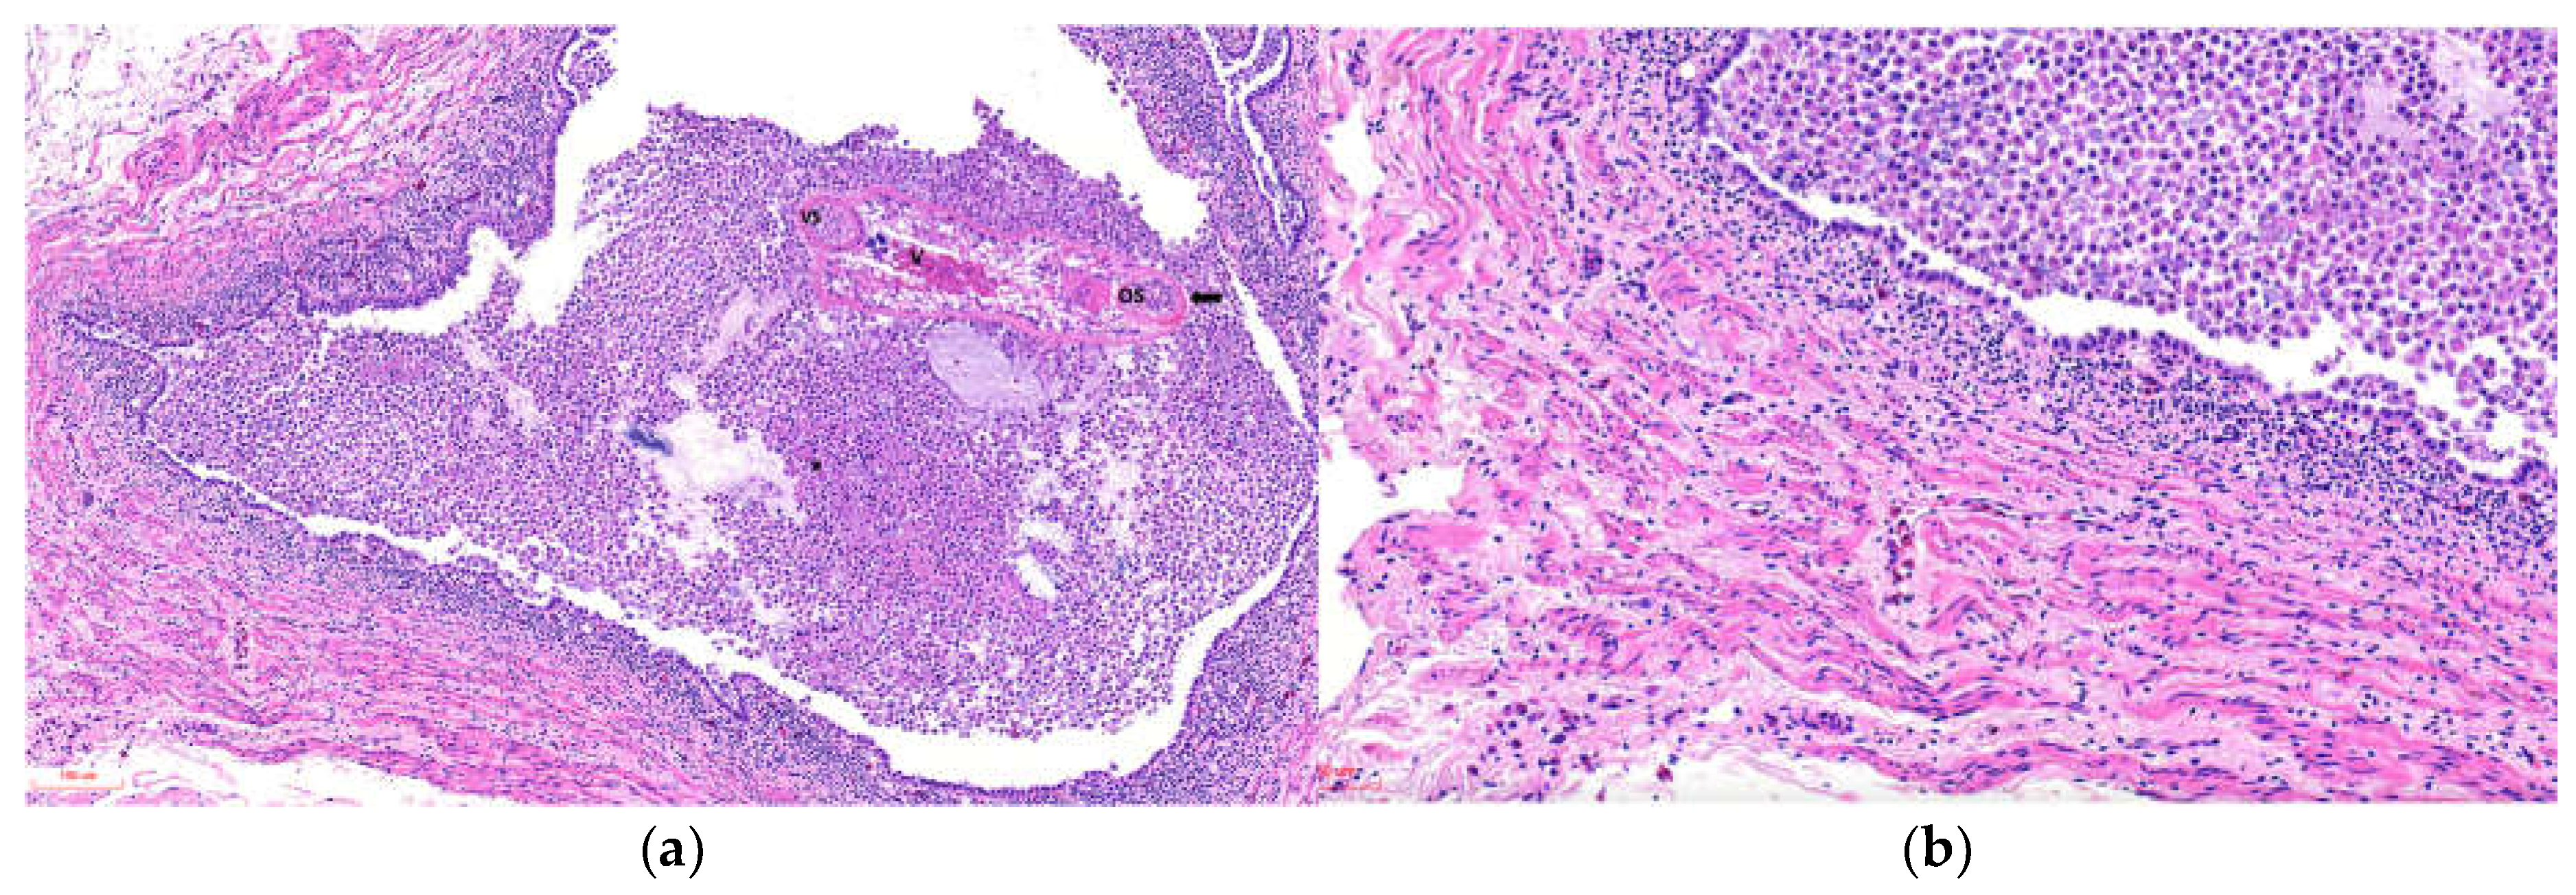

Histological analysis was performed on 5 penguins, and the finding summarized in Supplementary Table (Pathology). The main tubular lesions were characterized by degeneration of the epithelial cells of the collecting tubules, cystic dilatations containing one or two parasitic structures (Figure 2a), and adult parasites with uteri containing variable numbers of eggs (Figure 2b). Tubules containing urate crystals surrounded by lymphoplasmacytic inflammation with heterophils were observed in 3 of 5 animals. The interstitium exhibited moderate to marked diffuse fibrosis, with bands of mature collagenous tissue between tubular components (Figure 2a, Inset). The vascular component was hyperemic and congested, with multiple hemorrhagic foci.

Figure 2. Photomicrographs of histopathological sections of kidneys from Humboldt penguins with trematode-associated lesions in collecting tubules (H&E). (a) Animal ID 1: Arrow indicates dilated renal tubules measuring 350 × 219 µm (length × width) containing two parasitic structures at stage 2 within the tubular lumen. Asterisk: Peritubular tissue with marked diffuse interstitial lymphoplasmacytic inflammation (H&E). Inset: Green staining highlights interstitial collagen deposition (Masson’s trichrome). (b) Renal tubules dilated up to 1123 × 767 µm. Black arrow indicates the epithelial wall surrounding adult parasitic structures. Asterisk highlights a markedly dilated uterus containing multiple oval to round eggs covered by a thick eosinophilic capsule (Opercule); miracidia were occasionally observed within the eggs. V: vitellaria; OS: oral sucker. Adjacent renal tissue shows areas of mononuclear inflammation, degeneration, and necrosis.